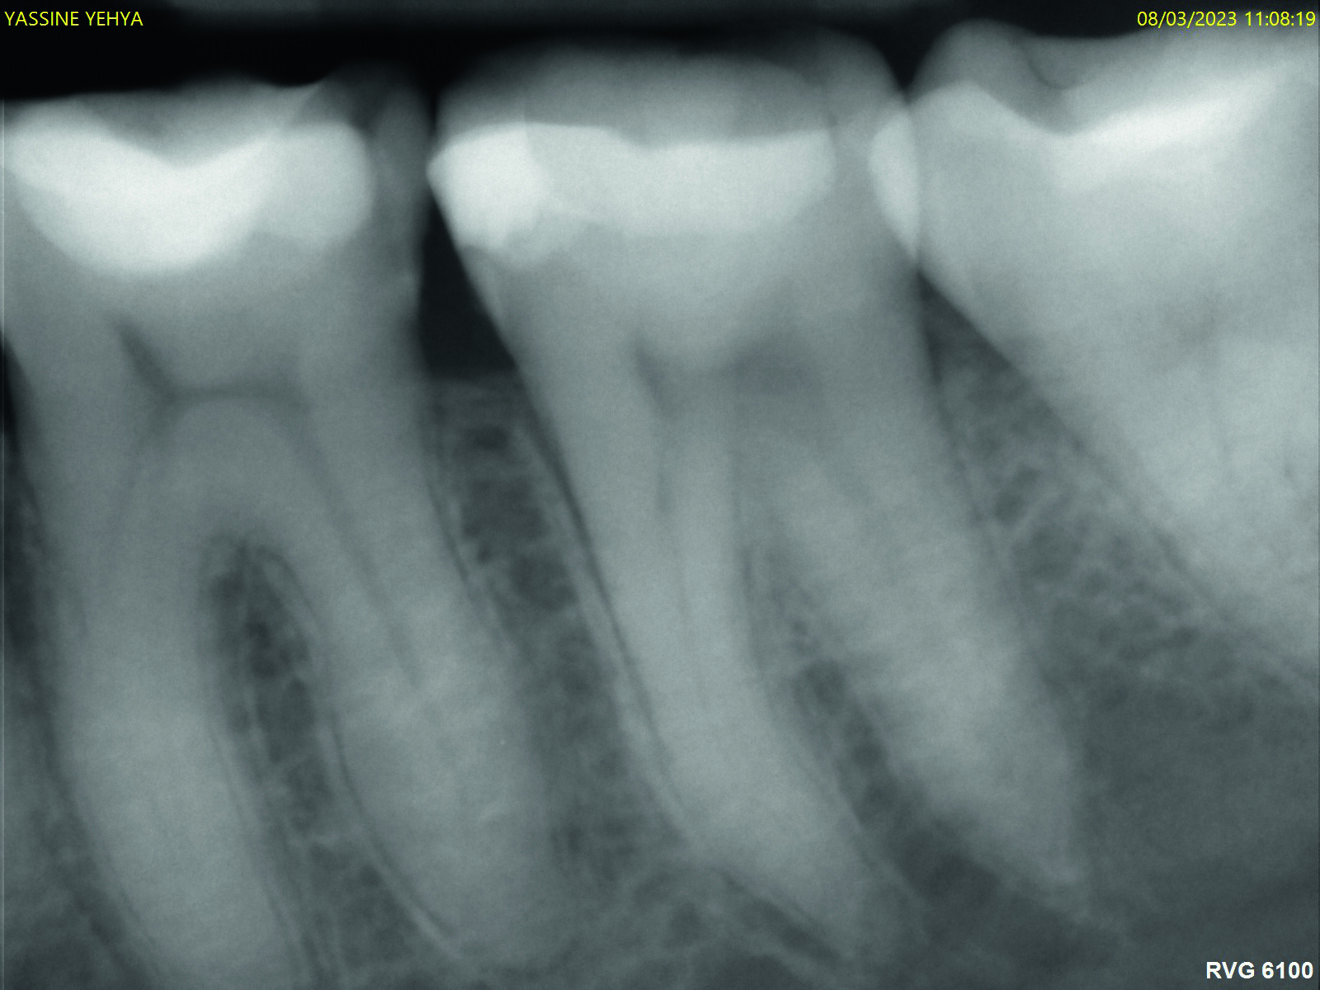

Les figures 9 et 10 montrent des images de radiographie numérique à un an et à douze ans de rappel après la reconstitution de la dent en technique Bio-Bulk Fill avec la Biodentine et le composite. La dent est vitale et aucune image périapicale n’est visible. Aucune rétraction pulpaire n’est observée, ce qui confirme la biocompatibilité de Biodentine.

Fig. 9 : Radio à un an de suivi.

Fig. 10 : Radio à 12 ans de suivi.